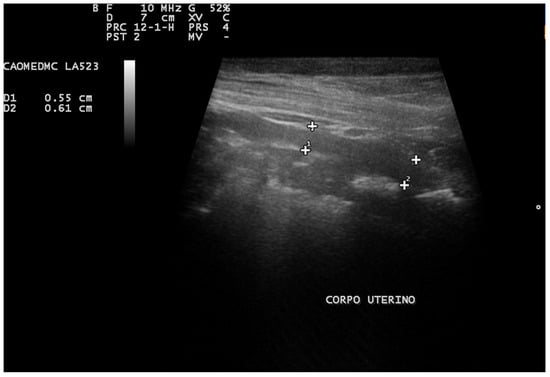

Ultrasonography has proven beneficial in identifying intrauterine fluid, even when the uterine diameter falls within the normal range (Figure 6). Additionally, it offers the advantage of revealing further pathological alterations in the tissue and ovaries, such as ovarian cysts or cystic endometrial hyperplasia [,].

Figure 6.

Abdominal ultrasound image of the uterus of a Pinscher. An enlarged left uterine horn measuring approximately 4.26 cm in diameter in the transverse plane is noted (cursors), with hypoechogenic content related to pyometra.